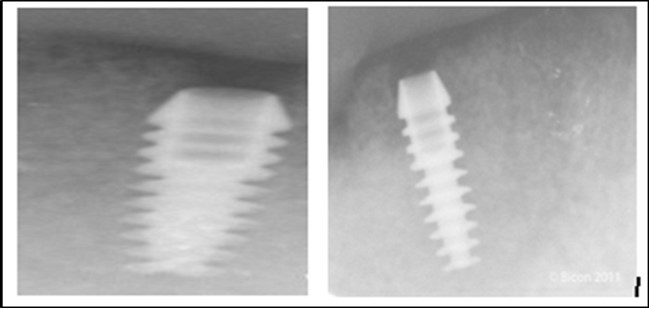

Post operatively after 3 months, osseointegration was evaluated clinically and radiographically (Figure 5a,b) and the implants were well prepared to receive the prosthesis. The second stage surgery was performed in which cover screws were removed and healing abutment were inserted into the implants (Figure 6). After a time period of two weeks, peri-implant soft tissue healing was examined, and existing denture was relined after relieving at the abutment site. Later, the healing abutment is removed using a 1.25 mm hex driver. Internal portion of the implant is irrigated and dried to make sure if it is free of debris and soft tissue. A periodontal probe was used to measure the gingival cuff height at the right and left canine site of implant location. Selected ball abutment were placed onto each implant using 1.25 mm hex driver and 30 Ncm torque wrench (Figure 7A).

Figure 5.a,b. Post-insertion radiographics in the mandibular area right,left,

Figure 6.Panoramic radiograph after the insertion of two implants